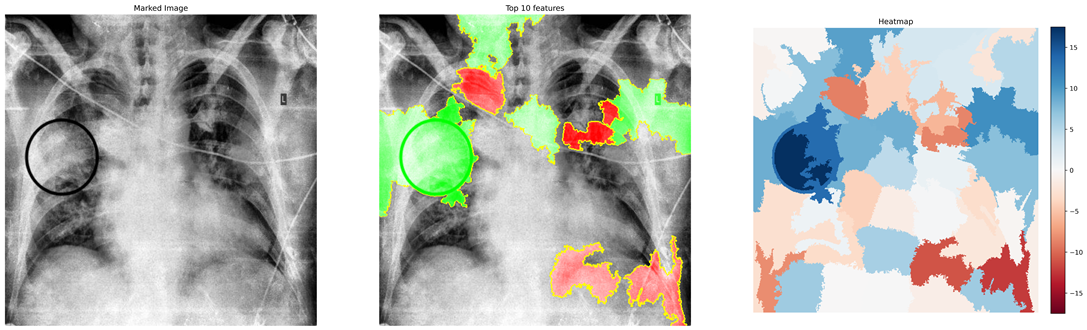

Figure 8 (a)-(c) shows images relating to COVID-19, Pneumonia, normal cases, respectively. Each subfigure in a row comprises three images of the same patient relating to a medical condition. In each row, the clinical condition has been marked by a radiologist in the first image. In the second image in the same row, the top 10 superpixels obtained using LIME have been marked using green and red colors. Superpixels contributing toward and against the predicted class appear in green and red colors, respectively. Finally, the third image in the same row depicts the LIME-generated heatmap corresponding to the second image. The intensity of the blue color of a particular region in the heatmap corresponds to its relative significance in predicting its class. A radiologist confirmed that in the case of Anteroposterior (AP) chest radiograph (Figure 8(a)), the ill-defined area of ground glass haze in the right lung parenchyma at mid-zone likely represents COVID-19. Similarly, in the Anteroposterior (AP) chest radiograph (Figure 8(b)), the wedge-shaped area of consolidation in the right lung parenchyma at the upper zone likely represents pneumonia. The radiologist confirmed that the regions (though not all) highlighted by LIME correspond to the affected regions in case of both COVID-19 and Pneumonia. This points to the applicability of COV-ELM in the identification of medical conditions such as pneumonia and COVID-19.